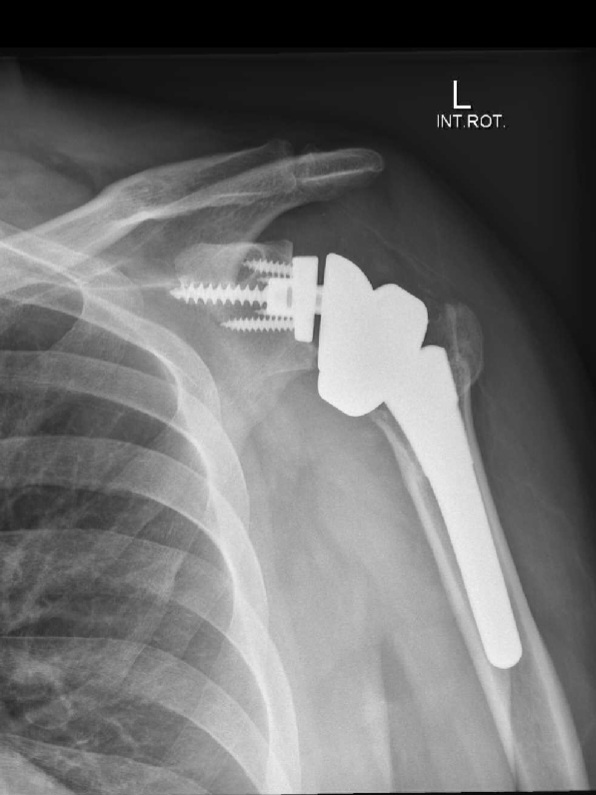

In late June 2024 I had a new shoulder installed; this is my three-month recovery diary.

By the end of the first week, I have nearly 90 degrees vertical movement (Flexion) of my arm, and I can rotate my forearm out to about 0 degrees rotation (external lateral rotation) ie forearm parallel to the ground and my hand straight out in front of me. Unfortunately, I don’t have the original measurements of my range before surgery, but it was fairly limited, with flexion of my arm only between about 90 and 100 degrees. I have to remember to ask my surgeon when I see him to see whether he has that.

An x-ray a few days later and all seems to be okay, and everything has settled down. I just need to keep an eye on it.

I’ve been curious why my arm is sore and weak in certain movements. It got me thinking about something the specialist said to me on my initial visit – when he looked at my x-ray he commented that my shoulder was dislocated and that it’s probably been like that for some time so the muscles/tendons would have adapted to that location. Therefore, I’m wondering whether this pain is more about my muscles and tendons readjusting to the new position … the right position.